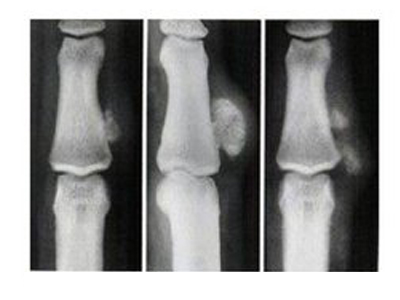

骨膜反应图 (9)

骨膜反应图 (8)

骨膜反应图 (7)

骨膜反应图 (6)